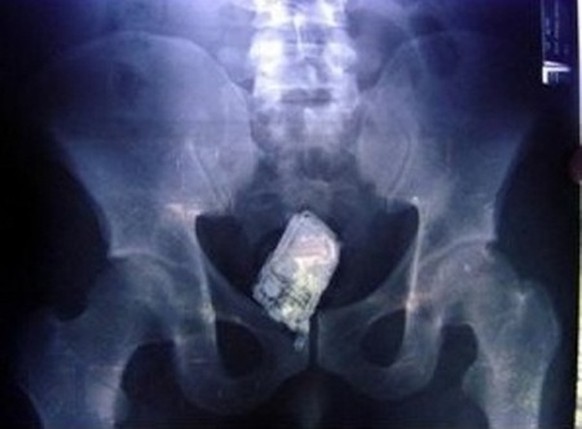

Ich kann grad nicht abheben

Ohne einer bestimmten Berufsgruppe einen Spleen für diese ungewöhnlichen Analpraktiken zu unterstellen, wird nun völlig vorurteilsfrei von einem weiteren Anwalt berichtet:

Sein Röntgenbild zeigt ein Mobiltelefon im Mastdarm. Wie kommt's?

Er habe geduscht; ja, mit dem Handy (das wasserfeste Samsung Galaxy S5 gab es da noch nicht) und dann sei er auf den Fliesen ausgerutscht und auf das Telefon gefallen – und schwups war es im Hintertürchen verschwunden.

Während die Ärzte den Fremdkörper herausmontierten, soll es noch dreimal geklingelt haben. Wir wollen hoffen, dass wenigstens der Klingelton nicht peinlich war.